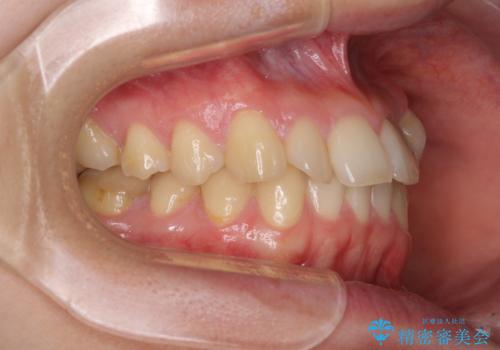

診査を行ったところ、下顎前歯が1本欠損しており、下顎歯列が上顎よりも小さくなっていることで、上顎にデコボコが生じていました。

口元を見ると抜歯をして突出感を改善するような状態ではなかったため、上顎歯列のデコボコを整えて、歯列全体を後方に移動させることでバランスを取ることとしました。

思っていた以上に上顎歯列を後方に移動させることができ、すっきりとした口元に仕上げることができました。